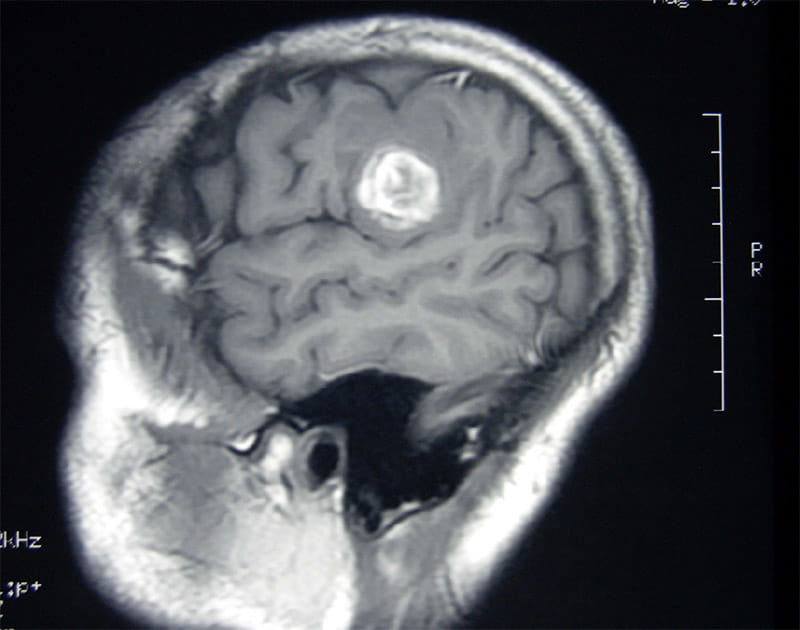

A brain scan showed the tumor. Had it grown a few more millimeters, it could've been fatal. Still, Schwartz's life remained in jeopardy because, by all indications, the tumor was most likely cancerous.

Schwartz had an abnormal cluster of tiny blood vessels known as a cavernous hemangioma. The tumor calcified, meaning that it grew a hard shell; the shell burst because the blood had nowhere else to go.